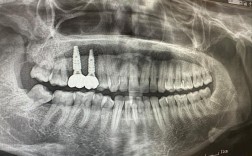

- 数字化诊疗: 大部分诊所都采用3D CBCT(锥形束CT)进行精准的术前评估,规划种植位置、角度和深度。数字化导板技术广泛应用,实现微创、精准种植,减少手术创伤和恢复时间。

- 系统化诊疗: 通常包含详细问诊、口腔检查、影像学评估(X光、CBCT)、治疗方案设计、费用预估、手术实施、戴牙、术后维护等完整流程。